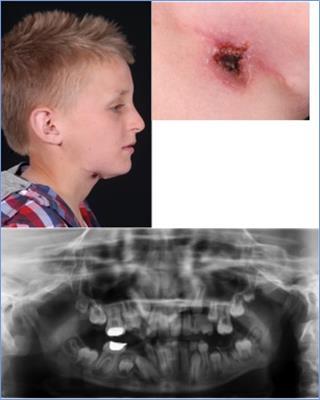

This was a referral made to the ENT department by a GP of a 12-year-old school boy who had a non healing wound in the right submandibular area. His GP and another ENT-Department had previously treated him for several months with topical antibiotic ointment and a surgical excision was also performed, however, the non healing area recurred shortly after the procedure.

On clinical examination, the lesion was 1cm in diameter and was located in the submandibular region on the right side. A 2.5 cm scar after attempted excision of the skin lesion was noted. A thorough history revealed, from the patient and his parents, multiple dental problems and treatments in the past (Figure 3 a-b). The patient was then referred to our department.

Figure 3a-c.Skin lesion right submental area, OPG mixed dentition with moderately restored LR6 and UR6, a big cavity around the LL6 and periapical radiolucany around LR6

The performed OPG showed a mixed dentition with moderately restored LR6 and UR6, a big cavity around the LL6 and periapical radiolucany around LR6 (Figure 3c). We performed a dental extraction of the LR6 and a punch biopsy of the lesion. The microbiological and histological results were similar to the first two cases described and shortly after the procedure the wound healed well with no recurring problems or lesions reported.